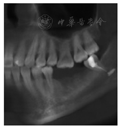

面暂封物完整,边缘密合,叩痛(-),不松动,牙龈未见明显异常。左下唇无肿胀不适等异常,有痛觉。曲面体层X线片及锥形束CT片示:

根管内充填物影像,根尖处下颌神经管内见长约4 mm条状充填物影像(图1)。

根管及下颌神经管内充填物影像

根管治疗时材料超填引起下牙槽神经损伤。根管超填材料可对下牙槽神经产生机械性刺激,压迫下牙槽神经并造成损伤,引起临床症状。本例根管充填材料为Vitapex,是一种氢氧化钙类根充糊剂,其主要成分为氢氧化钙、碘仿、硅油及其他赋形剂。影像学检查可见

根尖处下颌神经管内4 mm长条状充填物影像。尽管氢氧化钙类糊剂生物相容性良好,但大量超填可机械性压迫神经组织,导致神经损伤。由此推测本病例为超填的Vitapex直接压迫下牙槽神经导致下唇麻木。